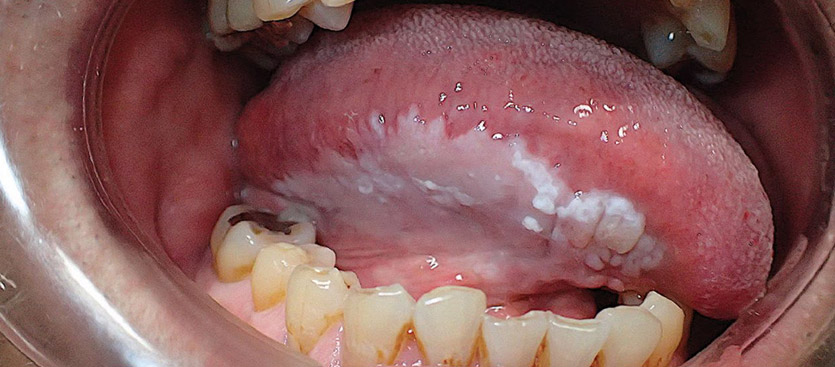

Leucoplasia

- Descrizione: Macchie biancastre che compaiono sulle mucose della Bocca, del Glande o della Vagina.